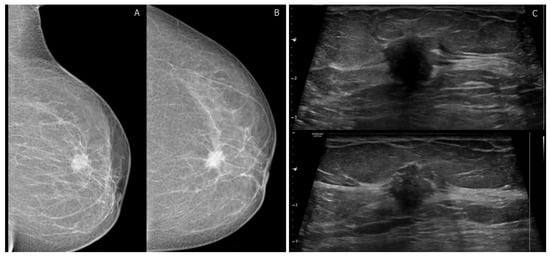

4.1. BI-RADS Mammography Findings

4.2. Advancements in Mammographic Imaging Techniques

4.3. BI-RADS Ultrasound Findings